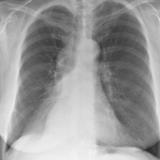

RLL Collapse 1 PA

Date: 02/28/2004

Views: 3445